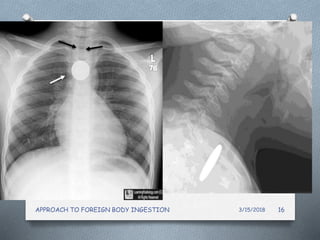

2.Neck /Chest/Abdominal Radiography

O Initial Investigation of choice

O Most ingested foreign bodies are radiopaque

(60%)

Determines :

O Presence

O Type

O location of the foreign body.

O Identifying possible complications

2. Where is the FB ?

AP: sagittal (end on) Lat: coronal (face )

• #17 . There is a coin (a magnified US nickel) (white arrow) in the esophagus, impacted at the level of the aortic arch. The coin exceeds the diameter of the trachea (black arrows) so that it can not lie within the trachea.

• #18 C- shaped cartilagenous ring ,defect posteriorly ,FB end on  Between swallows the esophagus is collapsed but the lumen can distend to approximately 2 cm in the anterior-posterior dimension and up to 3 cm laterally to accommodate a swallowed bolus. he cricopharyngeus (CP) muscle is a striated muscle attached to the cricoid cartilage. It forms a C-shaped muscular band that produces maximum tension in the anteroposterior direction and less tension in lateral direction.coin face en